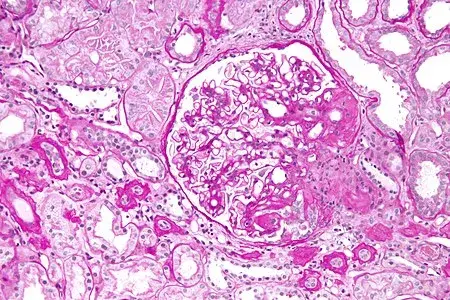

Injúria Renal Aguda (revisão Lancet 2025)

Injúria Renal Aguda (revisão Lancet 2025)